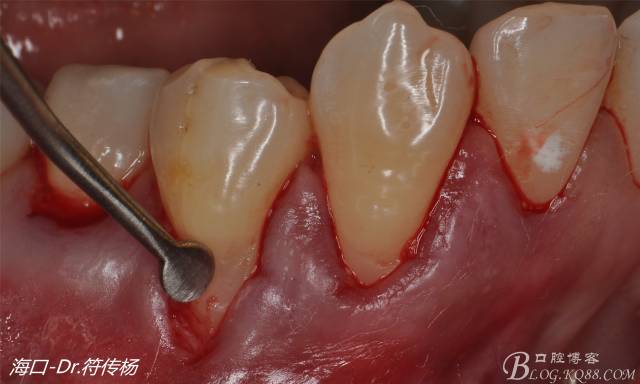

首先用顯微手術(shù)刀切斷手術(shù)范圍內(nèi)的牙周韌帶

然后使用下頜開隧刀剝離牙齦